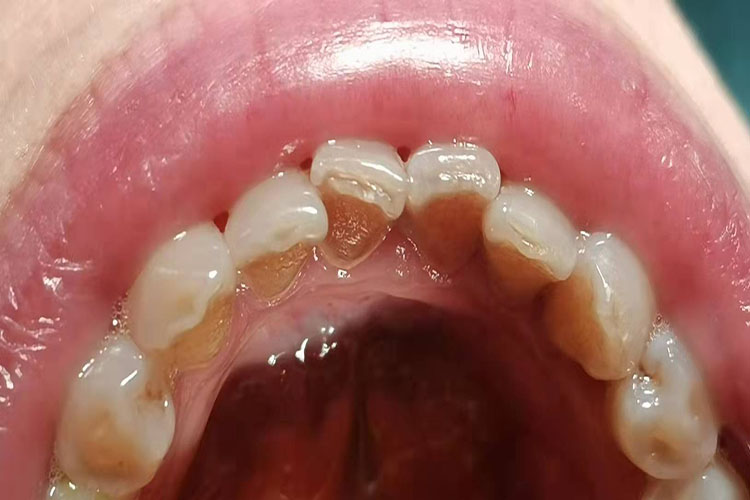

牙垢为白色或暗褐色,厚度各异,开始生长的部位常在牙面缺陷部位和不规则的表面,然后逐渐融合并沿龈缘生长,牙垢可填充邻面间隙。

龈上牙结石:常沉积在牙冠,直接可看到的牙结石称为龈上牙结石,呈黄或白色,一般体积较大,尤其是在与唾液腺导管开口相应处的牙面上沉积更多,如上颌第一磨牙颊面和下颌前牙的舌面。

龈下牙结石:多在龈缘以下,肉眼看不到,在X线片上可见。呈褐色或黑色,较龈上牙结石体积小而硬,一般与牙面的附着比龈上牙结石更牢固。